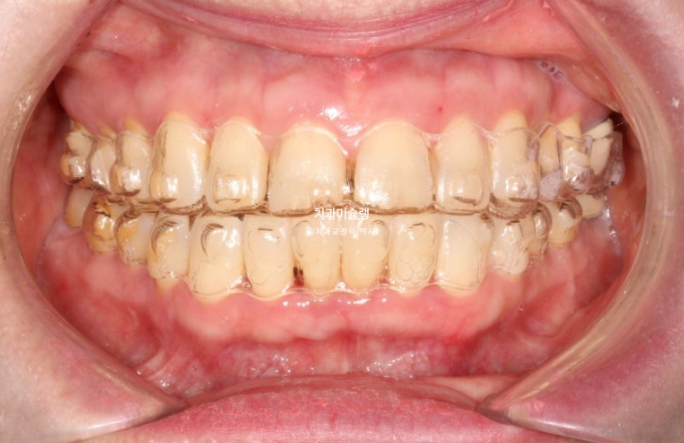

24년 7월 50대 환자분께서 교정치료를 위해 오셨습니다.

앞니가 세로 길이보다 가로길이가 더 긴, 한마디로 납작한 형태입니다.

치아 사이사이 벌어진 틈을 레진으로 메꿔놓고 지내온 것입니다.

충치로 인해 어금니들을 발치하게 되면서 교정치료를 병행하고자 오셨습니다.

일단 앞니 사이사이 레진을 제거해 보았습니다.

아래 앞니 사이 치석도 같이 제거합니다.